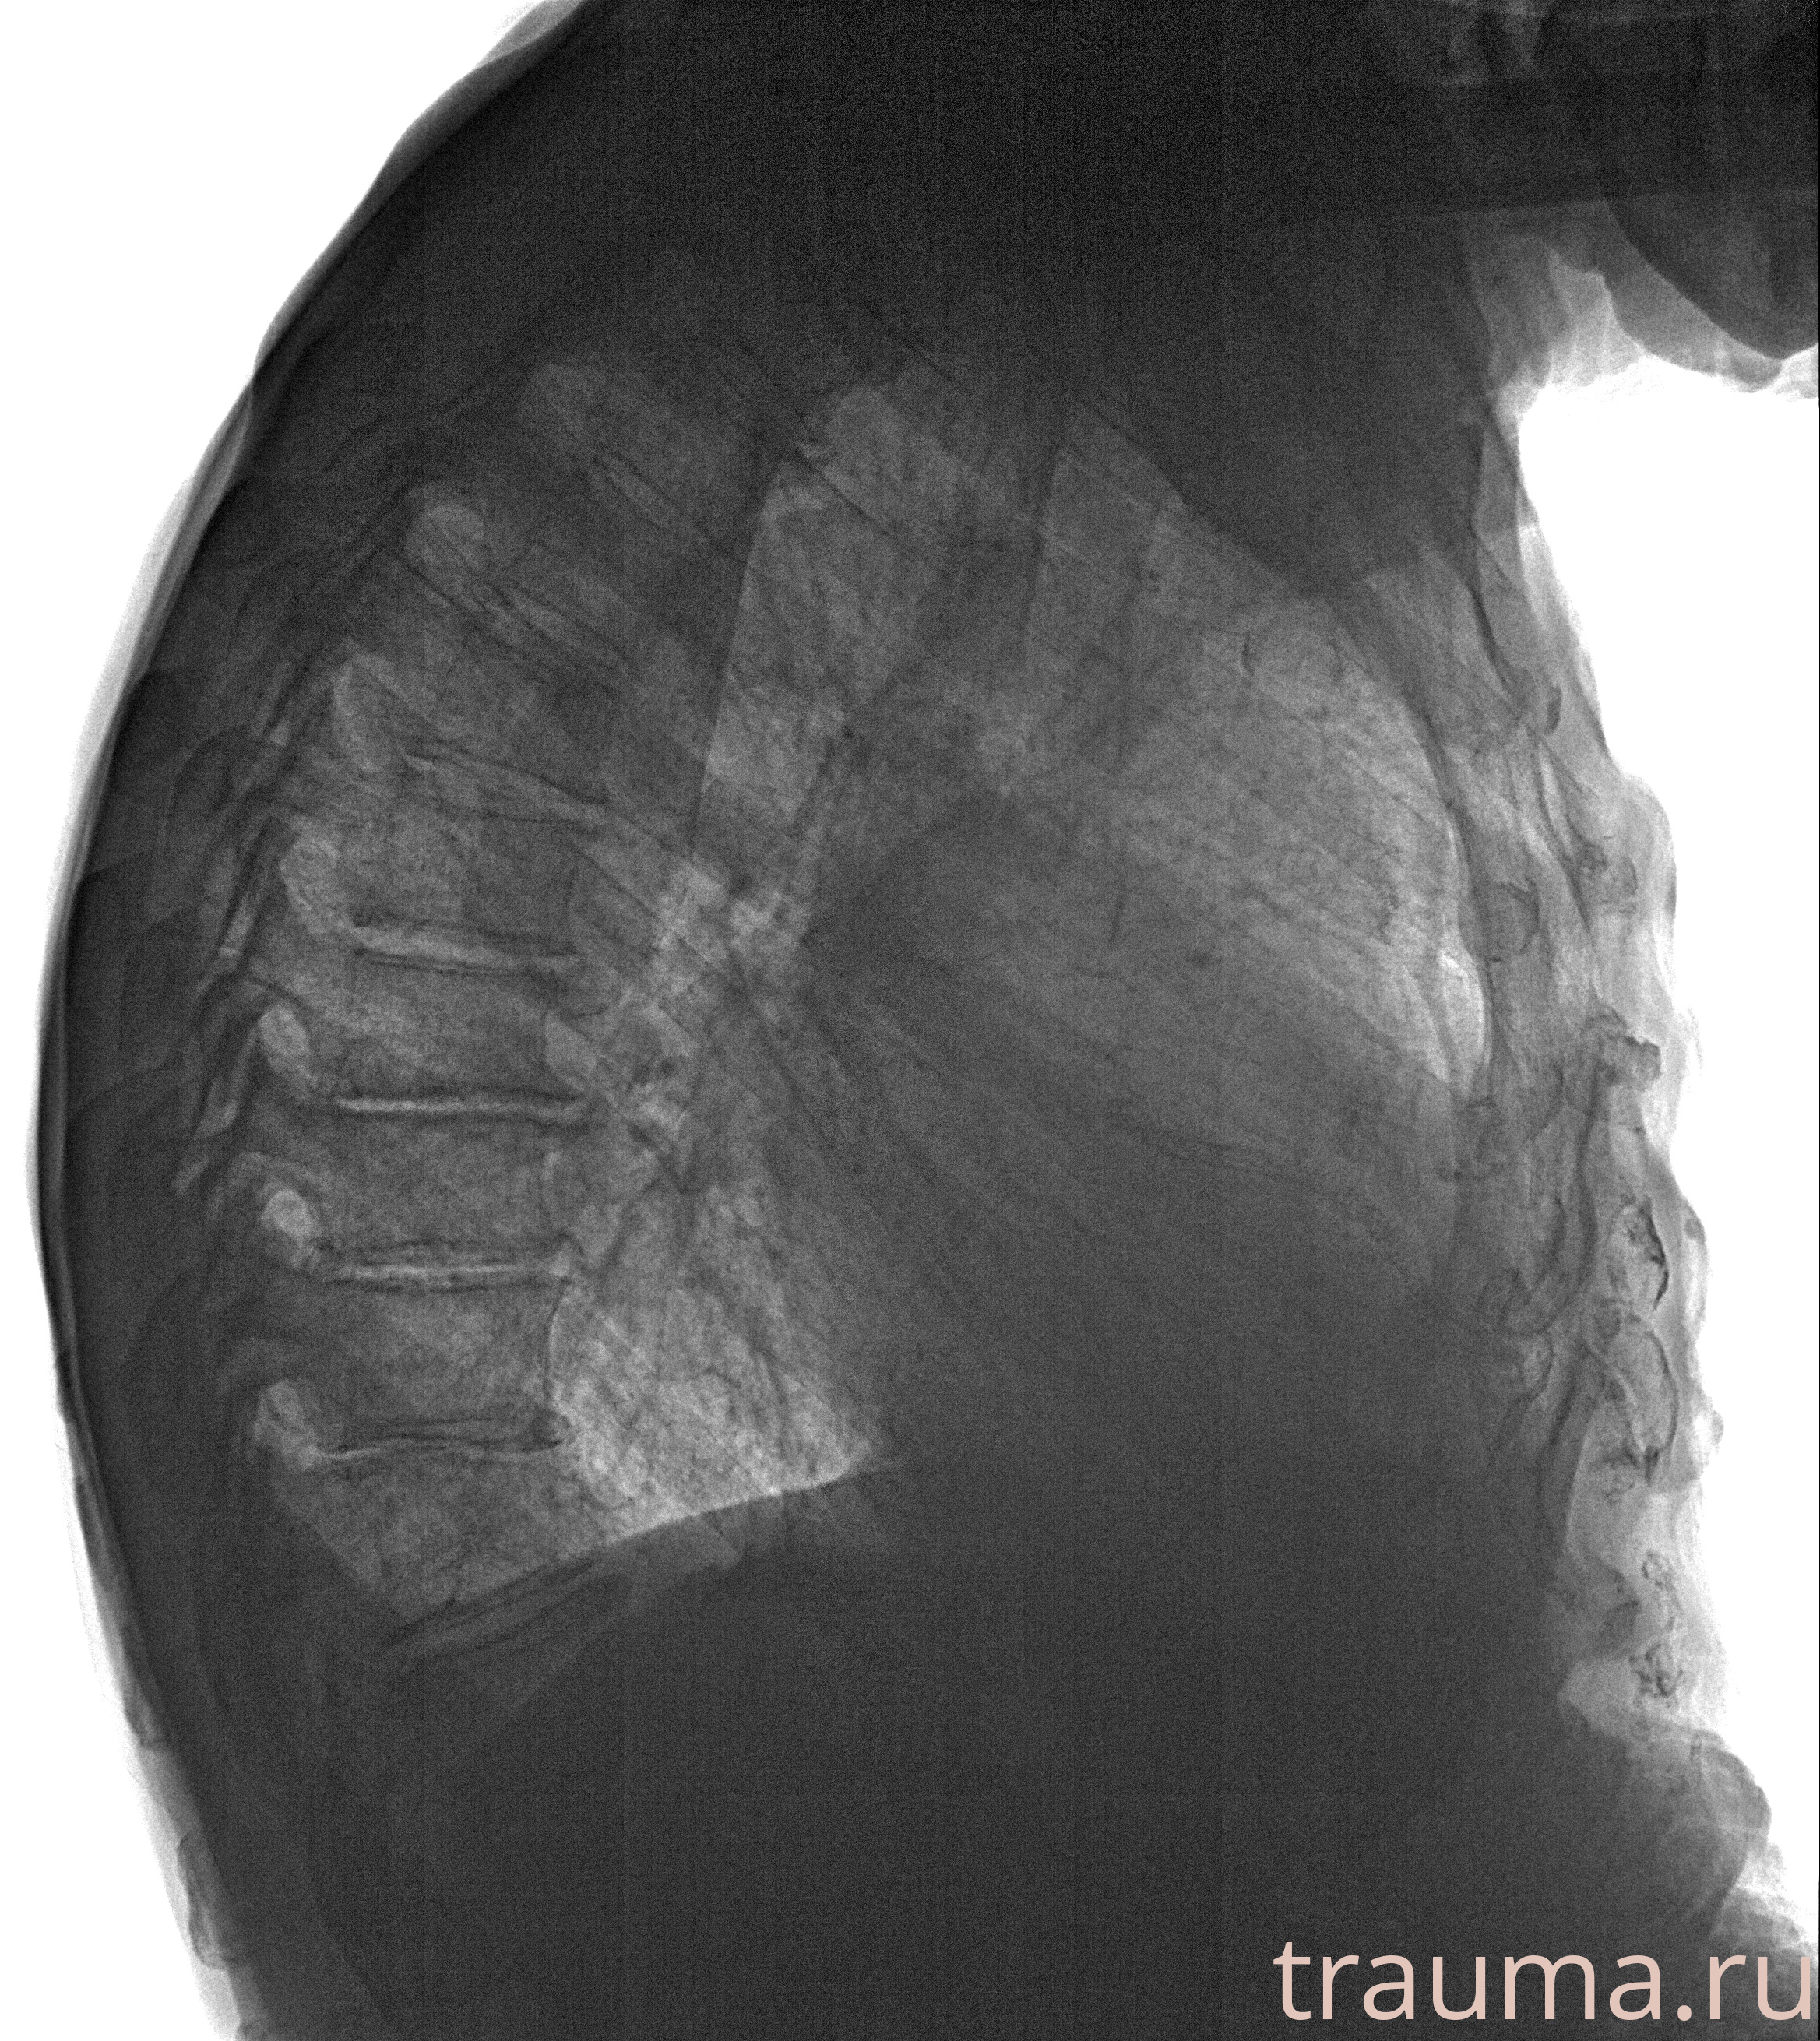

Рентген на дому: по вашему адресу приезжает врач-рентгенолог, травматолог-ортопед с мобильным рентгеновским аппаратом, проводит диагностику травмы или заболевания, делает необходимые рентгенограммы, дает рекомендации по дальнейшему лечению. Получить качественные снимки в домашних условиях возможно благодаря уникальной методике, разработанной МосРентген Центром для института  Склифосовского